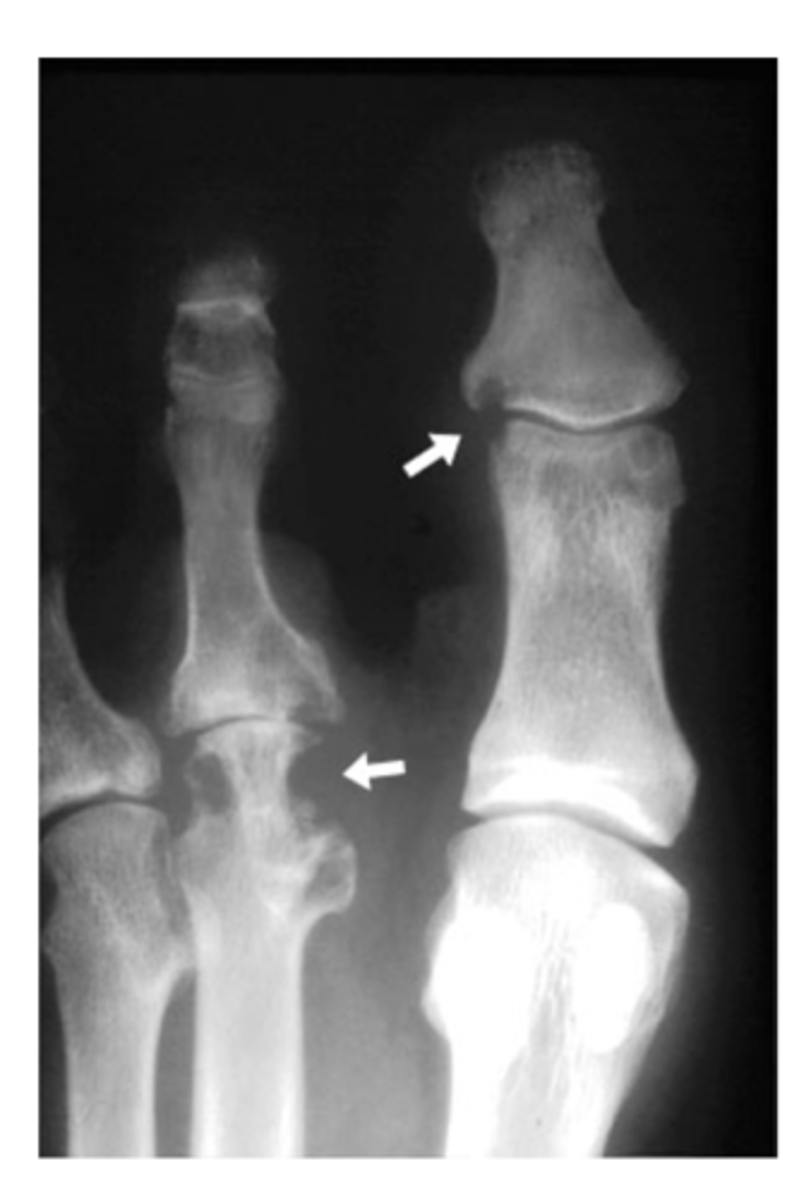

What are erosions? What do they indicate?

Scalloped, notched edges that indicate cartilage damage and wearing away of bone -- think rheumatic diseases (RA, PA, etc.)

What are epiphyseal plates? What do they indicate?

Cartilage in the middle of bone that gives the bone room to grow and solidifies over time -- think pediatric patients